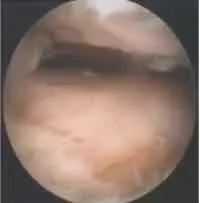

Un optique de 4–5 mm et à 30° est habituellement utilisé. Il faut débuter par la synovectomie de la chambre capsulaire antérieure, associée à la résection des ostéophytes de la marge antérieure du tibia. L’utilisation d’une sonde de radio-fréquence peut faciliter la libération du compartiment antérieur. La résection du cartilage jusqu’en os sous-chondral saignant (figure 20.4) doit se faire d’avant en arrière, le pied à angle droit.

La résection doit débuter au centre de la mortaise à l’aide d’ostéotomes, de ciseaux et de fraises motorisées. La littérature ne montre pas de supériorité des instrumentations motorisées par rapport aux ostéotomes ou ciseaux. Il faut maintenir le pied à angle droit et réséquer le cartilage en maintenant le manche des instruments perpendiculairement à la crête tibiale antérieure pour éviter une résection asymétrique du talus et du tibia.En cas d’équin talien, une libération des gouttières malléolaires peut être réalisée afin d’élargir la pince malléolaire, en faisant attention à ne pas fracturer la malléole médiale. Un allongement percutané du tendon d’Achille ou des gastrocnémiens peut également être nécessaire.La résection du plafond de la mortaise tibiale est habituellement réalisée avec des instruments « droits » (voir figure 20.4). La résection du 1/4 postérieur du dôme talien nécessite la mise en équin de la cheville et l’utilisation de curettes courbes. Le cartilage des gouttières malléolaires est systématiquement réséqué.

Comme pour l’arthroscopie antérieure, il faut débuter par la résection de la partie horizontale du dôme talien et du plafond de la mortaise jusqu’à exposer l’os sous-chondral (figure 20.8). Le cartilage des gouttières malléolaires est ensuite réséqué à la curette. La partie antérieure du dôme talien est réséquée en mettant la cheville en talus et en utilisant des curettes courbes. Le paquet vasculonerveux tibial antérieur est protégé par la capsule antérieure qui ne doit pas être excisée.

L’avivement ST se fait jusqu’en os sous-chondral, en utilisant des ostéotomes, des fraises motorisées et des curettes. Un contrôle peropératoire par amplificateur de brillance permet de valider la progression (figure 20.16).